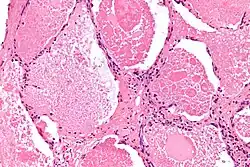

| Micrograph of pulmonary alveolar proteinosis, showing the characteristic airspace filling with focally dense globs referred to as chatter or dense bodies. H&E stain. | |

Lung washings or tissue for histopathologic analysis are most commonly obtained using bronchoalveolar lavage and/or lung biopsy.[13] Characteristic biopsy findings show filling of the alveoli (and sometimes terminal bronchioles) with an amorphous eosinophilic material, which stains strongly positive on PAS stain and the PAS diastase stain. The surrounding alveoli and pulmonary interstitium remain relatively normal.[14] Electron microscopy of the sample, although not typically performed due to impracticality, shows lamellated bodies representing surfactant.[15] An alternative diagnosis with similar histomorphologic findings is Pneumocystis jirovecii pneumonia.[15]

Lung washings characteristically yield a fluid which is "milky"composition. Under the microscope, samples show 20-50 micrometer PAS-positive globules on a background of finely granular or amorphous PAS-positive material. There is typically a low numbers of macrophages and inflammatory cells (although this is variable).[14][15]